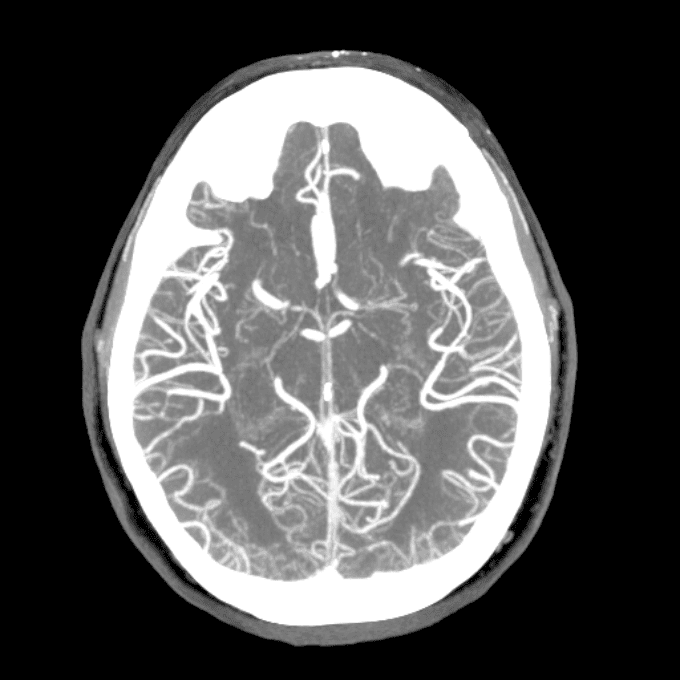

Practice

Simulates call by including subtle or difficult cases and some normals.